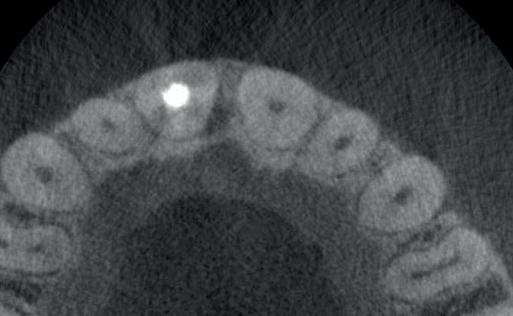

4: Horizontale doorsnede CBCT met radiolucentie mesiopalatinaal van de 11

de patiënt zich zorgen maakt over deze toevalsbevinding, wil hij de 11 laten beoordelen door een endodontoloog.

Er wordt een CBCT gemaakt die een laesie aan de mesiopalatinale zijde van 11 laat zien (afbeelding 4).

15: Horizontale doorsnede CBCT laat bot ingroei zien

16: Sagittale doorsnede CBCT

Bij de controle na 3 jaar (afbeelding 13) is de pocketdiepte verder afgenomen tot 4 mm (afbeelding 14), de gingiva is stevig en er is geen bloeding na sonderen. De CBCT laat duidelijk ingroei van het bot zien (afbeelding 15 en 16). De laatste röntgenfoto dateert van 14 jaar na de behandeling (afbeelding 17), er zijn geen klachten en de parodontale conditie is stabiel.